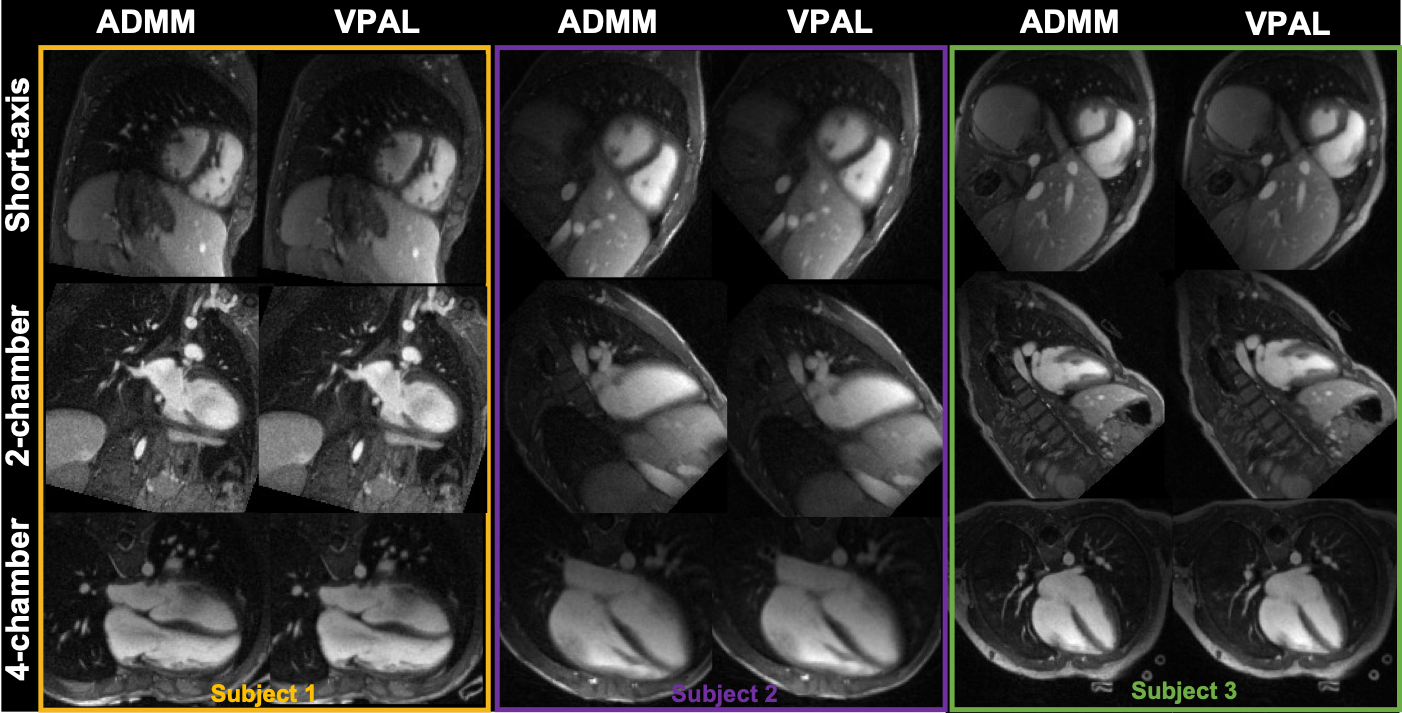

In the 15 pediatric subjects, there are a varying number of cardiac frames, 17+/4 (mean and standard deviation), and the 4 (same for all subjects) respiratory frames to be reconstructed in the 5D free-running framework. The reformatted views of three example in-vivo subjects’ ADMM and VPAL reconstructions are shown in Figure 4.

The radiologist graded all cardiac cines in 2-chamber, 4-chamber and mid-short-axis cines to have good to excellent diagnostic values (3-4). The distribution of the image quality scores on ADMM and VPAL cines is shown in Figure 8. In 2-chamber reformatted cardiac cine images, ADMM images scored 3.8 0.4 and VPAL scored 3.9 0.3 (p=0.16). In 4-chamber reformatted images, ADMM scored 3.9 0.4 and VPAL scored 3.9 0.4 (p = 1), and in mid-short-axis images, ADMM scored 3.7 0.5 and VPAL scored 3.7 0.5 (p = 0.33). No significant differences were found in the radiologist’s image quality ratings between ADMM and VPAL.